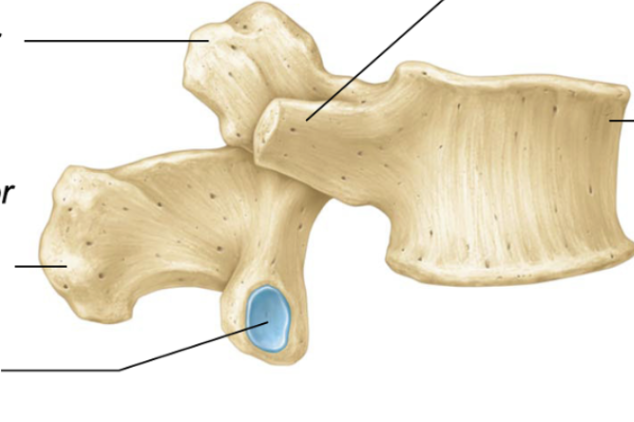

annulus fibrosis

Acts like a barrier to keep inner part in

nucleus pulposus

absorbs any shock/stress

thoracic vertebrae

lumbar vertebrae